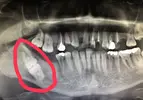

Çene Kistleri